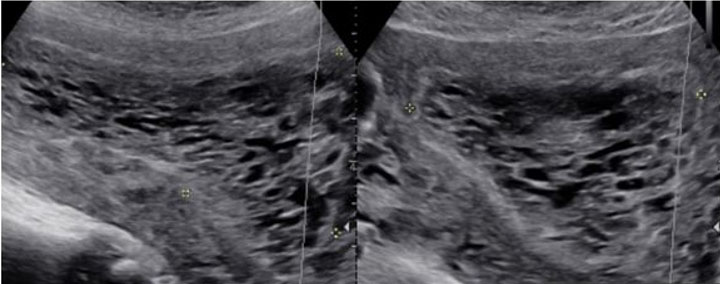

The patient’s serum quantitative bHCG is 59,401 with blood type O+. The remaining laboratory studies were unremarkable. Transvaginal ultrasound showed no evidence of intrauterine gestation with complex heterogenous material within the uterus measuring 8.8×4.9×6.8 cm (Figure 1 and Figure 2). The patient was counseled appropriately about suction dilatation and curettage in the context of suspected complete molar pregnancy, given the absence of a fetus on transvaginal sonogram, elevated serum bHCG level, vaginal spotting, and new onset hypertension. The patient underwent an uncomplicated suction dilatation and curettage. Intra-operatively, tan-colored grape-like vesicles measuring between 1 and 2 cm were noted in the suction tubing (Figure 3). Post-procedure bedside sonogram was performed and revealed a thin endometrial stripe. The patient tolerated the surgery well and was discharged in good health after appropriate clearance from postoperative anesthesia care unit. Post-operatively, appropriate pre-eclampsia laboratory tests were conducted due to the patient’s elevated blood pressure, revealing a urine protein-creatinine ratio of 0.245 and normal serum laboratory results. Given persistently elevated blood pressures post-procedure, the patient was started on Labetalol 200 mg twice daily upon discharge. Pathology assessment of the resected surgical specimen confirmed complete molar pregnancy. The patient’s blood pressures normalized one-month post-procedure and she is no longer taking the prescribed anti-hypertensive. Her post-operative bHCG was closely followed weekly over the course of eight weeks until the value was less than 1.0.

Figure 2: Sagittal view (L) and transverse view (R) of the uterus demonstrating “snow-storm like” appearance of a complete molar pregnancy via transvaginal ultrasound.

Imaging through transvaginal ultrasound often can diagnose molar pregnancy before 12 weeks. Ultrasound can show either a honeycomb or a fine vascular appearance [7]. Ultrasound confirmation of a complete molar pregnancy after 12 weeks of gestation is characterized by a lack of fetal parts and scant embryonal development with a classic “snowstorm-like” appearance within the uterus. Specifically, the “snowstorm-like” appearance is indicative of hydropic villi and intrauterine hemorrhage. The ovaries can often contain multiple large theca-lutein cysts secondary to ovarian hyperstimulation from elevated bHCG levels [8]. Meanwhile, ultrasound confirmation of a partial mole can be slightly more difficult as there is usually the presence of a fetus and/or a large placenta [8].